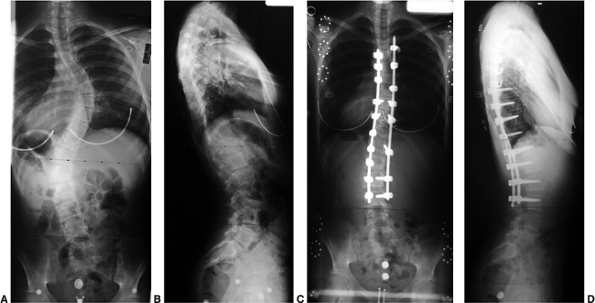

Figure 18.4 A: This posteroanterior radiograph demonstrates the appearance of a double thoracic scoliosis curve pattern. B:

The lateral radiograph demonstrates the relatively straight sagittal profile of the thoracic spine with loss of normal thoracic kyphosis. This is a common feature of adolescent idiopathic scoliosis. C: The clinical appearance of this patient demonstrates a prominent scapula. However, this is not caused by kyphosis but by the rotational deformity of the ribs, which secondarily makes the right scapula more prominent. Additionally, a left upper thoracic trapezial fullness can be appreciated in this patient, caused by the left upper thoracic curvature.  |